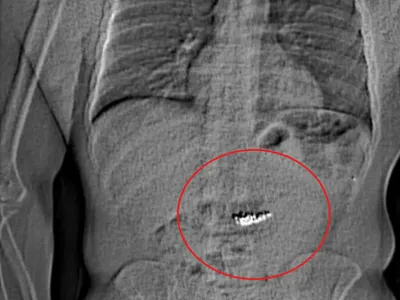

Actualitate Ca să scape basma curată, un hoț a înghițit bijuteria furată. Valora 700.000 euro Ca să scape basma curată, un hoț a înghițit bijuteria furată. Valora 700.000 euro. A fost arestat de polițiști cu doar câteva secunde după ce a înghițit-o.